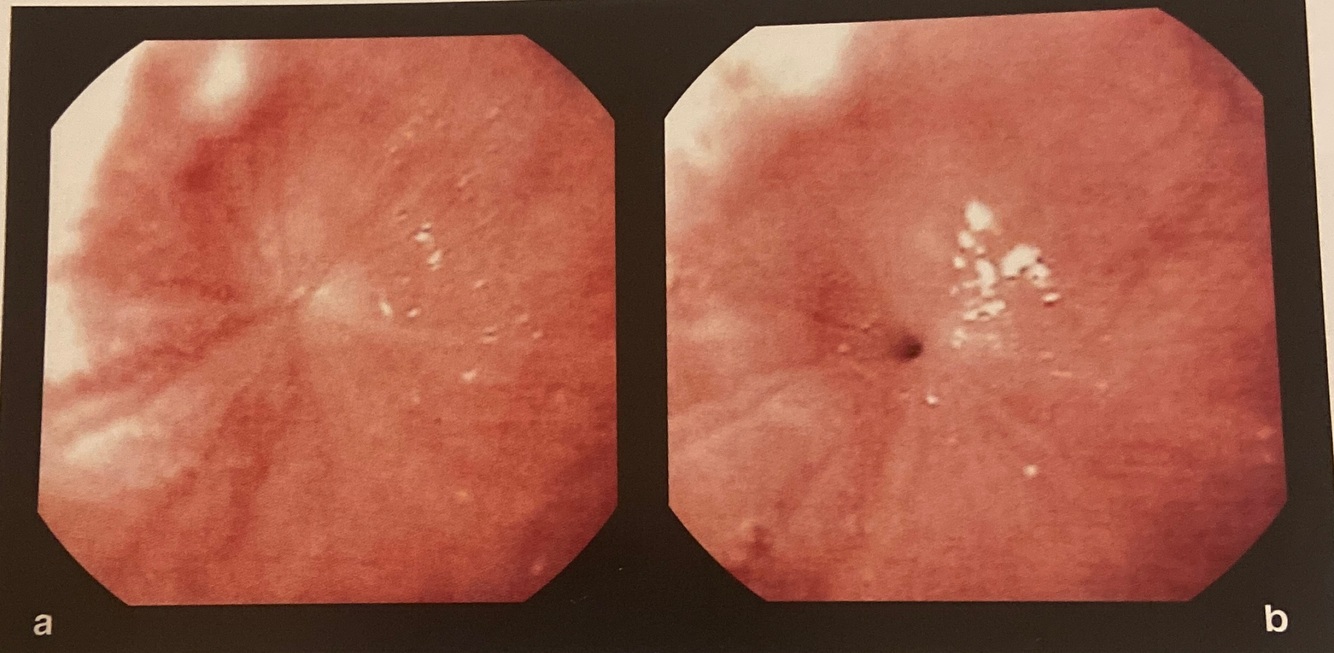

a e b Endoscopia de coristoma completo do esôfago

How well did you know this?